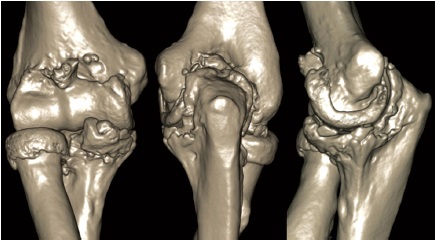

Второй этап. Выполняют МСКТ обоих локтевых суставов пациента, и на их основе создают трехмерную реконструкцию (рис. 2).

Рис. 2. Трехмерная реконструкция пораженного оссификатами локтевого сустава, выполненная на основе МСКТ (передний, задний, латеральный отделы сустава) также не позволяет полностью визуализировать оссификаты

Fig. 2. 3D reconstruction of the elbow joint with ossificates performed using MSCT data (anterior, posterior, lateral joint sections) also does not allow to fully visualize ossificates